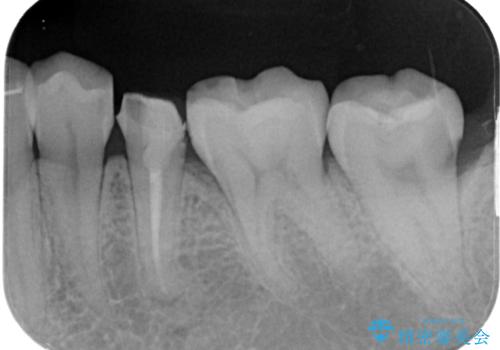

- 左下の被せものが割れたとのことで来院された患者様です。検査の結果、左下の前から4番目の歯はセラミックインレー修復、左下の5番目のところはオールセラミッククラウンによる補綴治療を行っていくことにしました。

拡大鏡視野下で被せもの、虫歯の除去を行い、オールセラミッククラウン、セラミックインレーに適した形に整えました。

患者様のご希望により左下5番目の根管治療は行っておりません。